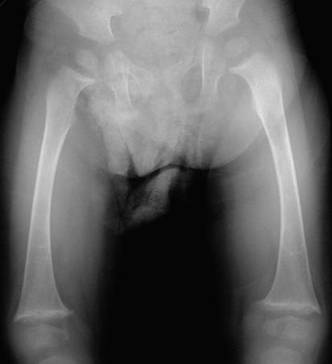

.jpg) الأعراض: تختلف نسبة ودرجة ظهور الأعراض من شخص لآخر، فالبعض تظهر عليه العلامات المرضية بشكل كبير من اليوم الأول للولادة، وآخرون يتم اكتشاف حالاتهم بالصدفة لعدم ظهور الأعراض عليهم. قد تكون الأعراض واضحة لدى الطفل، وغير واضحة لدى أحد الوالدين o الضعف وعدم زيادة الوزن o ضعف النمو- الطول - نتيجة المقاومة ضد هرمون النمو o معالم الوجه المميزة والتي قد لا تكون واضحة خلال السنة الأولى من العمر مثل: الذقن الصغير البارز، العينان الغائرتان، الجبهة العريضة o خلل في الكبد حيث تكون الأقنية الصفراوية قليلة، لذلك يلاحظ وجود اليرقان من خلال اصفرار بياض العين والجلد o يكون لون البراز فاتح مثل الصلصال - لعدم وجود الإفرازات الصفراوية في البراز o يكون لون البول أصفر غامق o تضخم حجم الكبد والطحال o تراكم الكولسترول مما يؤدي لارتفاع ضغط الدم o عدم القدرة على امتصاص الفيتامينات الذهنية مما يؤدي للكساح وضعف التجلط o زيادة مستوى حمض الصفراء serum bile acids مما يؤدي لحدوث الحكة o عيوب خلقية في القلب خاصة ضيق الشريان الرئوي pulmonary stenosis o شكل غير معتاد لعظام العمود الفقري حيث يكون لها شكل الفراشة butterfly vertebrae في 50% من الحالات o التخلف الفكري بدرجات متفاوتة o صغر حجم الخصية والذكر نتيجة ضعف الهرمونات الجنسية Hypogonadism o مشاكل في الكلى o مشاكل في العيون في 75% من الحالات o السكري نتيجة لفشل البنكرياس o عادة ما يعيشون حتى مرحلة الشباب o من الأسباب الرئيسة للوفاة هو الجلطات الدماغية

.jpg) .jpg) التشخيص: o زيادة نسبة الصفراء المباشر في الدم نتيجة انسداد القناة الصفراوية o زيادة مستوى حمض الصفراء في الدم serum bile acids o زيادة مدة التجلط الدموي prothrombin time o زيادة نسبة الكوليستيرول والدهون الثلاثية في الدم o زيادة تحليل وظائف الكبد خاصة الفوسفيت الحمضي alkaline phosphatase o الأشعة الصوتية للقلب تظهر العيوب الخلقية o ارتفاع ضغط الدم o تغير وظائف الكلى o تحليل الكروموسومات Chromosomal analysis o خزعة الكبد - ندرة في القناة الصفراوية o الأشعة للعظام لمعرفة العيوب العظمية في العمود الفقري والأضلع والأطراف o الأشعة الصوتية للكبد لمعرفة التغيرات أو حدوث تحول سرطاني لها hepatoma o فحص العيون لمعرفة المشاكل المصاحبة